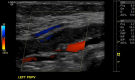

Ultrasound in the emergency department has long been recognized as a powerful screening and diagnostic tool for both physicians and radiologists. In the emergency department, since time is of the essence, it becomes a critical tool in triaging patients. Over the years, ultrasound has gained several advantages over other modalities because of its non-ionizing radiation, portability, accessibility, non-invasive method and simpler learning curve. As a result, ultrasound has become one of the most frequently used diagnostic tools in the emergency department by non-radiologists. The value of ultrasound is implemented in every acute ailment in the emergency department such as trauma, acute abdomen, acute pelvic pain, acute scrotal pain, appendicitis in children and acute deep venous thrombosis. Our objective is to discuss the benefit of using ultrasound as the primary modality for each of these diseases.